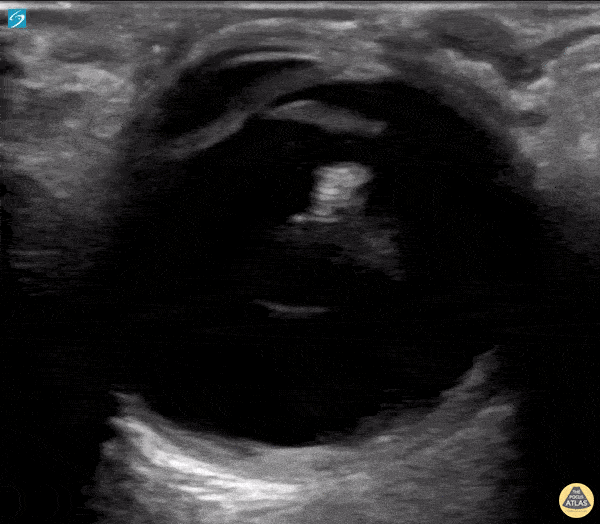

Orbital - Intraoccular Lens Subluxation

A 50 year old male with a prior history of bilateral intraoccular lens (IOL) transplants presented to our ED with sudden onset foggy vision in his right eye while getting out of the shower. He was unable to participate in visual acuity due to the extent of his blurred. POCUS demonstrated “iridodonesis” and a provisional diagnosis of IOL subluxation/dislocation was made. Ophthalmology was consulted and confirmed the diagnosis. Dr. Piaseczny, PGY4 Emergency Medicine, Queen's University, Kingston, Ontario, Canada